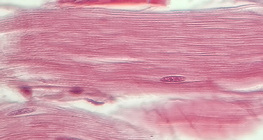

zumiranje: 400x